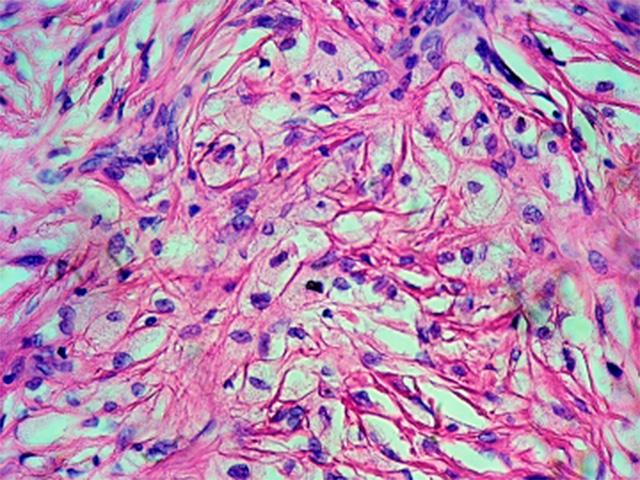

Casos clínicos